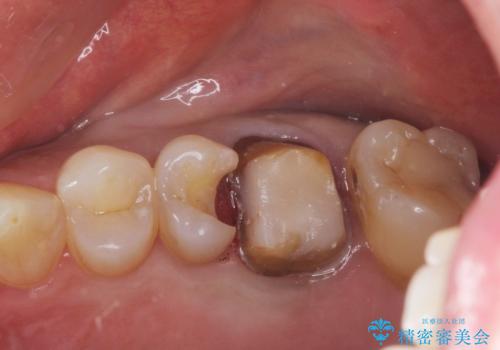

金属をセラミックにしたい、根管治療も行ったケース

- 金属をセラミックにしたいと、他の患者様の紹介でいらっしゃいました。

左上6の金属のかぶせものをセラミックにかえるにあたり、根管治療からやり直しています。

左上5の虫歯もセラミックインレーにて修復しました。